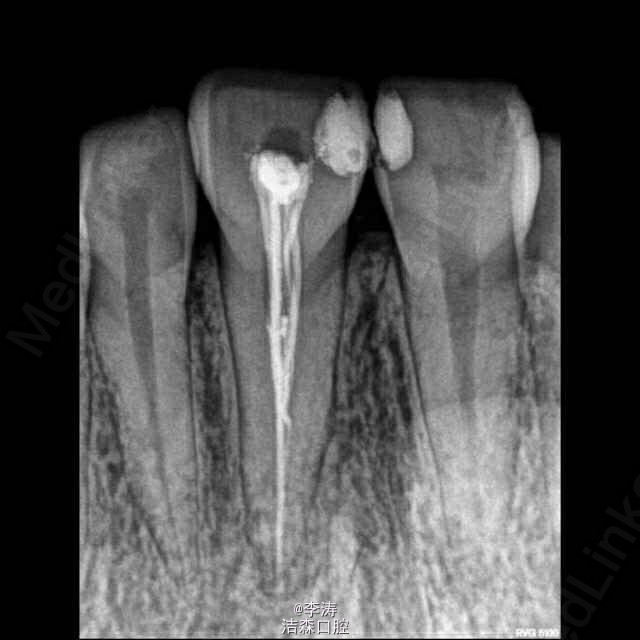

根管治疗超充之后怎么补救?

11牙超填,已行纤维桩修复,未行冠修复,患者无症状。应该怎么补救???

下前牙根管治疗,超充?糊剂?